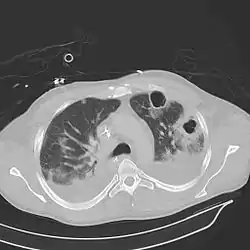

![]() تصوير مقطعي محوسب للصدر ويُلاحظ ذات الرئة ثنائية مع خراجات، انصبابات وتجاويف. لرجل عمره 37 سنة. تصوير مقطعي محوسب للصدر ويُلاحظ ذات الرئة ثنائية مع خراجات، انصبابات وتجاويف. لرجل عمره 37 سنة. | |